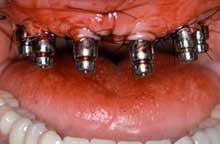

Combined treatment of mandibular and maxillary atrophy.